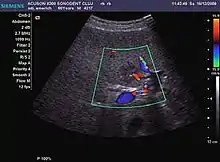

Tumor characterization is a complex process based on a sum of criteria leading towards tumor nature definition. Often, other diagnostic procedures, especially interventional ones are no longer necessary. Tumor characterization using the ultrasound method will be based on the following elements: consistency (solid, liquid, mixed), echogenicity, structure appearance (homogeneous or heterogeneous), delineation from adjacent liver parenchyma (capsular, imprecise), elasticity, posterior acoustic enhancement effect, the relation with neighboring organs or structures (displacement, invasion), vasculature (presence and characteristics on Doppler ultrasonography and contrast-enhanced ultrasound (CEUS).

The substrate on which the tumor condition develops (if the liver is normal or if there is evidence of diffuse liver disease) and the developing context (oncology, septic) are also added. Particular attention should be paid to the analysis of the circulatory bed. Microcirculation investigation allows for discrimination between benign and malignant tumors. Characteristic elements of malignant circulation are vascular density, presence of vessels with irregular paths and size, some of them intercommunicating, some others blocked in the end with "glove finger" appearance, the presence of arterio-arterial and arterio-venous shunts, lack or incompetence of arterial precapillary sphincter made up of smooth musculatures. Diagnosis and characterization of liver tumors require a distinct approach for each group of conditions, using the available procedures discussed above for each of them. The correlation with the medical history, the patient's clinical and functional (biochemical and hematological) status are important elements that should also be considered.